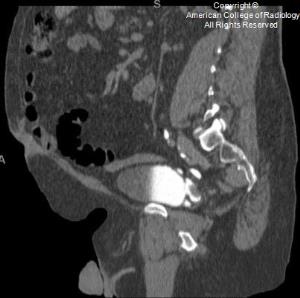

Read the Bulletin » Read the JACRTest your clinical knowledge with the daily Case in Point program, which gives you the opportunity each weekday to work through a subspecialty case.